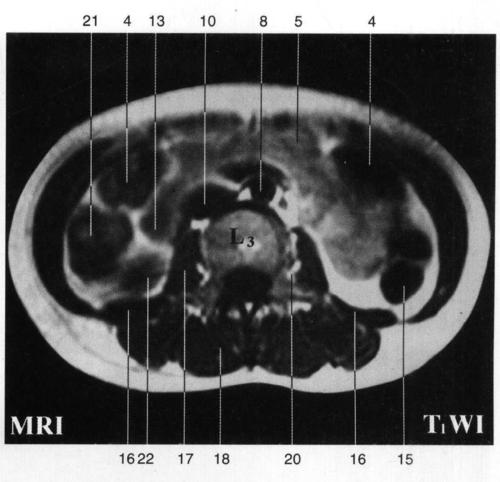

竖脊肌 erector spinae 19.马尾 cauda equina 20.

竖脊肌 erector spinae 17.马尾 cauda equina 18.